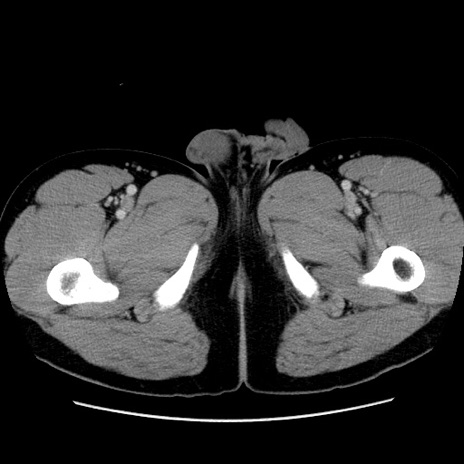

症例4(横断像)

【症例】30歳代男性

【主訴】腹痛、嘔吐

【現病歴】昨晩から突然の腹痛あり、その後嘔吐、軟便も出現。腹痛が改善しないため救急搬送となる。2日前にしめ鯖の食事歴あり。

【身体所見】意識清明、苦悶様、BP 135/90mmHg、BT 35.7℃、腹部:平坦、やや硬、心窩部〜臍部に自発痛、圧痛あり、筋性防御+、反跳痛-

【データ】WBC 8100、CRP 0.57